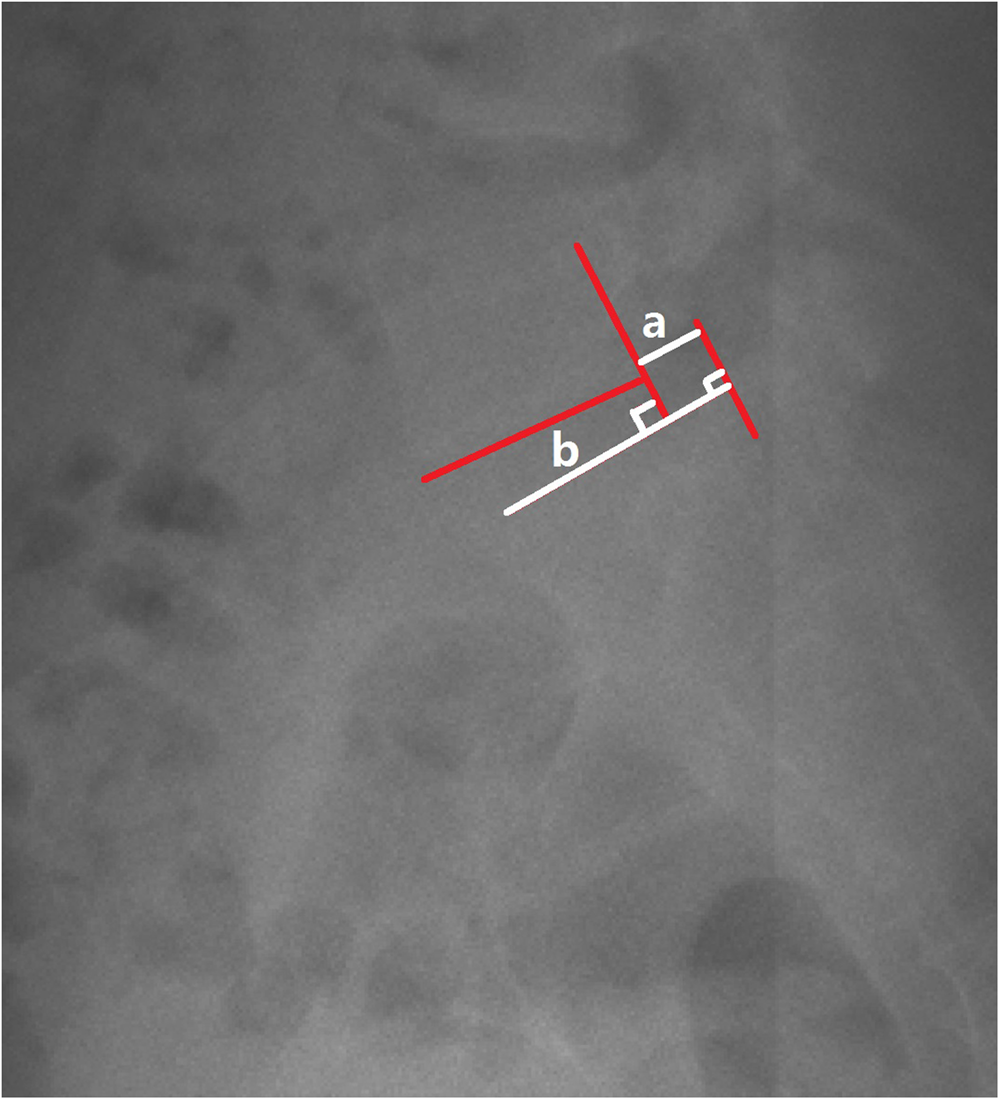

Demonstrated the measurement of slip percentage.